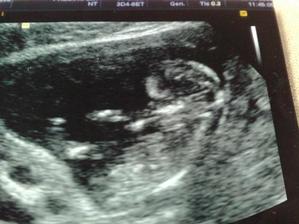

Od poslední operace jsem užívala Utrogestan po něm mi nebylo moc dobře, tak se nasadila Provera.Po ní mám stejně MS nepravidelnou.Koncem května jsme se rozhodli navštívit Car.Chtěli jsme do Zlína, pač to máme blíž, ale moje pojišťovna s nimi nemá slouvu, takže nic.Takže jsme hledali a našli si v Olomouci Fertimed.Objednali jsme se na konzultaci 2.7.2008.Konzultace proběhla bez problému, jen vyšetření, které proběhlo před přítelem bylo pro něj trochu překvapením.Příteli udělali SPG kde zjistily že je v pořadku.Posléze nám byli zjištěny Ureoplazmata, tak jsme s přítelem zobali ATB. Nebylo nám ani jednomu znich dobře. A měli jsme zakázáno snažilkování. 20.8.2008 jsem měla jít na svou první IUI, ale bylo mi zjištěno, že nemám ovulaci.Tak s toho sešlo.9.9.2008 jsem měla vyšetření průchodnosti.12.9.2008 jsem šla na KO a na výsledky.Vše je ok, vše mám průchodný i po všech operacích a ureoplazmatech.A snažilkování opět zakázáno kvůli zahojení.Poprvé mi byly dány stimulace Clostilbegyt.Tak teď už jen čekám na mrchu.Mrcha dorazila 3.10. takže opět smůla,7.10. začínám zobat Clostilbegyt.Po sexíku po něm trochu špinim, ale je to možná ještě brzy kvůli tomu vyšetření průchodnosti. 13.10. jedu do Car na KO hm tak jsem zvědavá jak to na mě zapůsobilo.Uvidíme co budu mít v bříšku 🙂) KO dopadla dobře mám 4 vajíčka o velikosti 1.4cm a sliznici 5.5cm. 17.10.08 v 13hod máme první inseminaci.Po píchnutí pregnylu mi není dobře a ještě k tomu ten divný klobouček co zavádějí.19.10. kontrola a druhá inseminace.29.10. Kontrola v CAr a nalezena další cysta.Další cyklus tedy proběhne bez Clostíku.19.11. kontrola máme ovulaci a 2 folikuly.24.11. třetí inseminace opět je mi špatně po pregnylu a ten klobouček hrůza 26.11. čtvrtá inseminace opět je mi špatně po pregnylu, odebrána krev na tumorové markry,štítnou žlázu a cytologie.5.12. kontrola není nic vidět, krev v pořádku aspoň se nemusím bát že mám v sobě rakovinové buňky,štítná žláza též v pořádku.Cytologie bude po Vánocích.Přes Vánoce nepracují tudíž se budeme snažilkovat doma.Přes Vánoce jsem si zkoušela porvé udělat ovulační testy.Testy mi vycházely // jeden mi vyšel i s /// což bylo tedy opravdu divné.5.1.09 jsem si udělala poslední ovu test s// nu jenže 6.1.09 jsem dostala pěkně silnou MS.12.1.09 jsem byla u své obvoní dr, která mi vzala krev a moč.13.1.09 jsem byla u své gynekoložky a ta mi řekla že jsem měla opět cystu která byla už prasklá.Moje obvodní lékařka mi řekla ,moč je v pořádku,ale v krvi mi chybí červené barvivo v červených krvinkách.Tak jsem si koupila železo s kyselinou listovou.21.1.kontrola v CAR řekli mi že mám 2folikuly, odmítla jsem IVF, a objednala se do FN Olomouc (10.března 11:45) k dr. Dostálovy, výsledky z cytologie dopadly dobře. 10.3. první poradna u doc.Dostála, vše probíhalo v pořádku, zatím jsme jen dotsali papíry na IUI. 23.3. 13dc sliznice 10mm, ovarium vlevo 14+PCO, ovarium vpravo 17mm, 25.3.-27.3. plánovaný styk. 21.4.09 13dc sliznice 10,3mm, vpravo 19x26mm folikl, dnes IUI, následující den plánovaný styk,zavádění Utrogestanu po 8dní. 13.5. poradna s doc. Dostálem, výsledky horm. profilu ok, spg ok, domluva na IVF ( srpen 09 ), dostala jsem veškeré léky a poučení. 18.5. 13dc sliznice 11mm, ovarium vlevo 17mm, vpravo nic, 19.-20.5.09 plánovaný styk.21.5. UTZ sliznice 7,4mm, ovaria 0, 1.6.09 HCG 103,9. 18.6.09 UTZ 6tt embryo s pravidelnou akcí srdeční. 25.6.09 UTZ 7tt vše ok. 9.7.09 UTZ 9tt těhu průkazka. 3.8.09 Prediko UTZ 13tt vše ok jen nemáme změřenou nosní kůstku. 6.8.09 13tt kontrola, 26.8.09 16tt kontrola 1,5kg, 10.9.09 18+1 kontrola 0,5kg, 24.9.09 20+1 kontrola první pohyby 2,5kg, 25.9.09 Prediko UTZ 20+2, 15.10.09 23+1 1,5kg, 2.11.09 test na cukrovku už nikdy v životě!, dietu nedržím ale musím chodit na ko, 5.11.09 26+1 2kg,